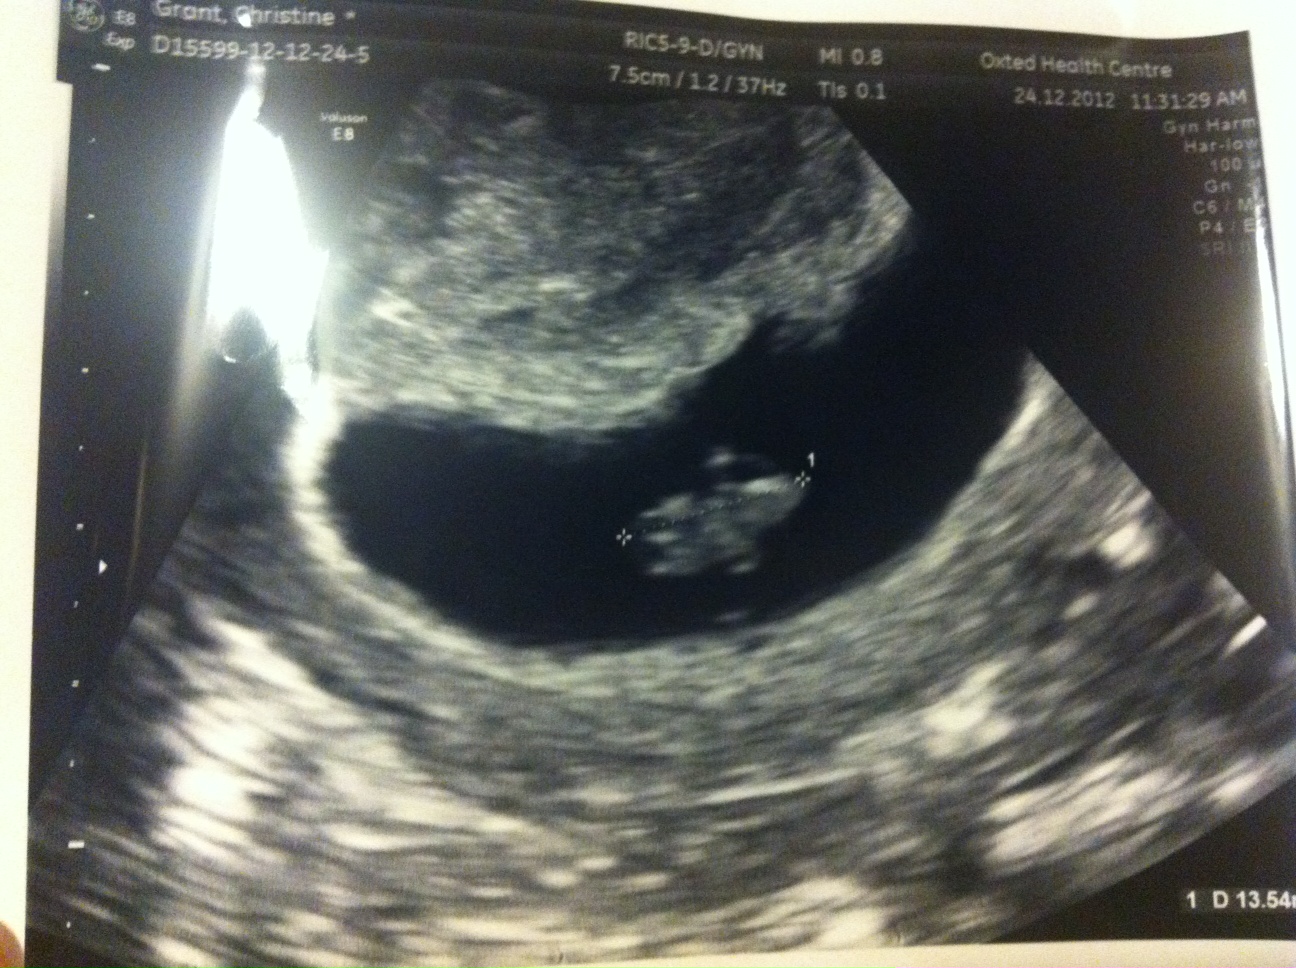

These are the pictures I got:

Attachment 7589

I then had a second (private) scan 6 days later and there were still 2 sacs yet this time it appeared there was a healthy baby in the big sac with yolk sac and heart beat and a CRL measurement of 13.8mm making it 7+5. The smaller sac still had an embryo and a tiny fetal pole but no heartbeat measured 3.6mm